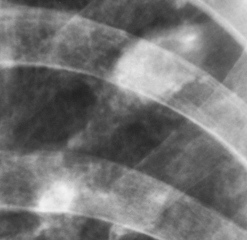

Иллюстрации 2, 3. Фрагменты рентгенограммы с увеличением. Четко определяется неоднородность структуры фокусной тени, с нечеткостью контура, с наличием эксцентрически расположенной полостью распада.